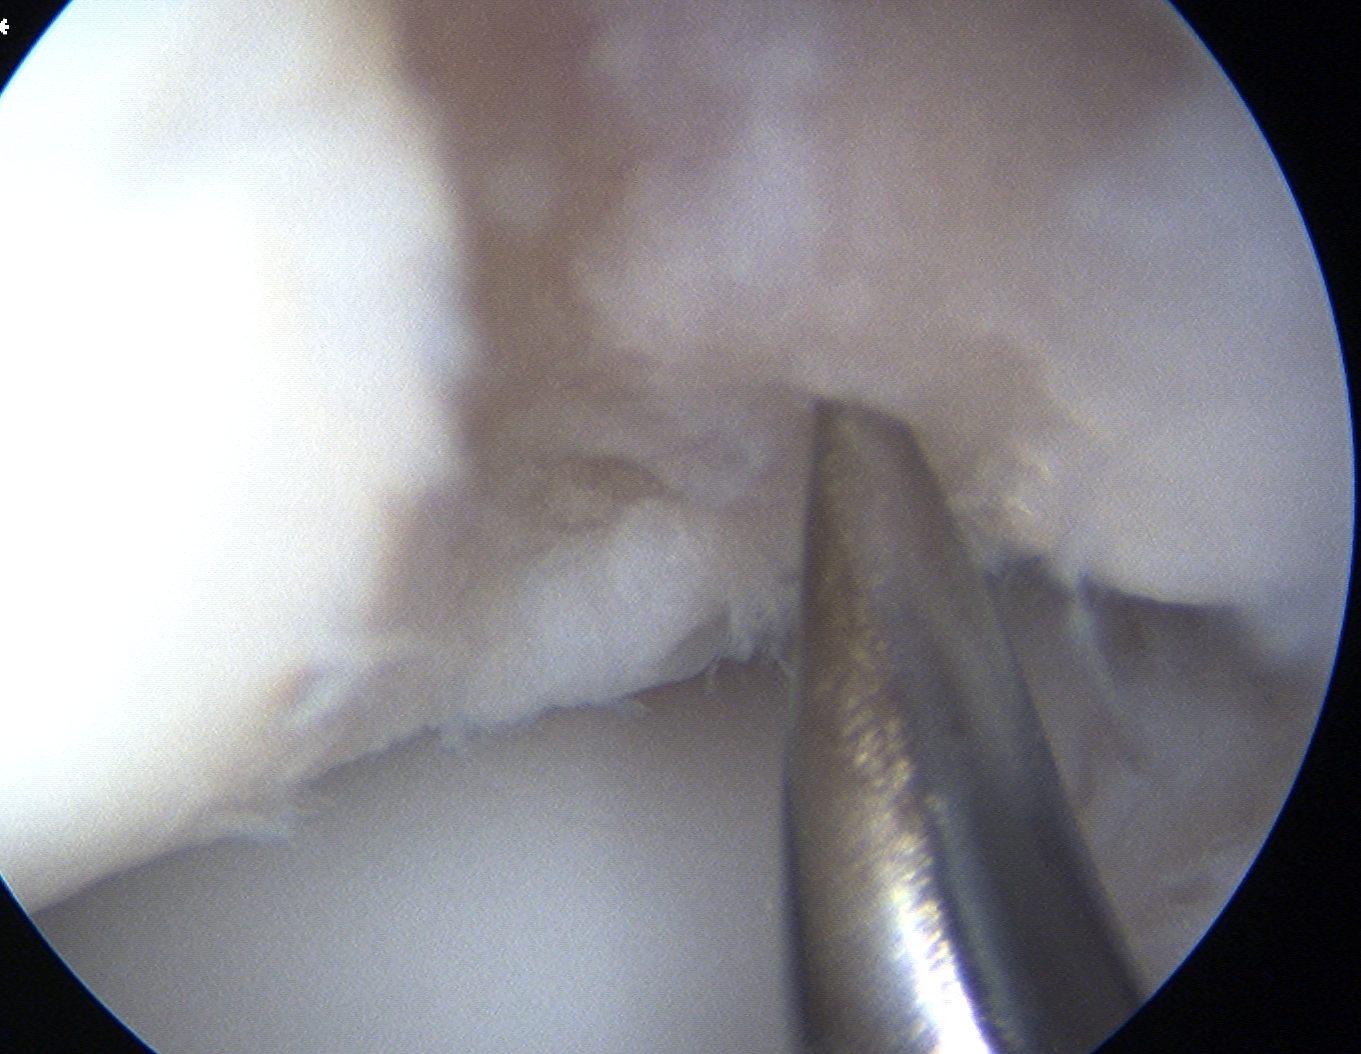

Capitellar OCD viewed via anterior portals, being drilled in retrograde fashion using ACL jig

Arthroscopic technique

1. Anterograde

2. Retrograde using ACL jig